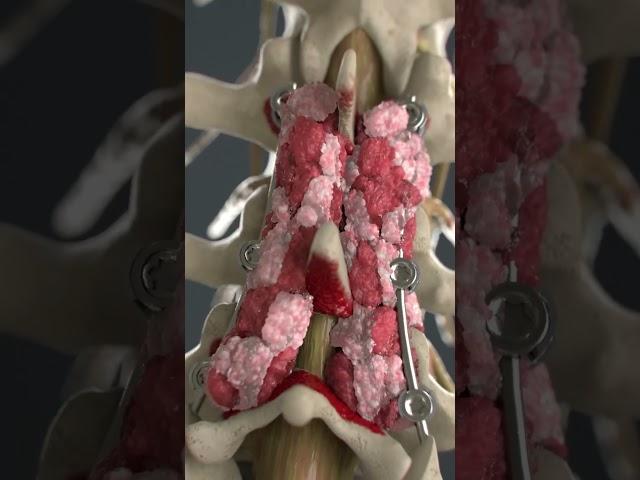

𝑫𝒓 𝑺𝒉𝒂𝒌𝒕𝒊'𝒔 𝑭𝒆𝒓𝒕𝒊𝒍𝒊𝒕𝒚 & 𝑮𝒚𝒏𝒂𝒆-𝒍𝒂𝒑𝒂𝒓𝒐𝒔𝒄𝒐𝒑𝒚, 𝑩𝒂𝒓𝒈𝒂𝒓𝒉.

𝑫𝒓 𝑺𝒉𝒂𝒌𝒕𝒊'𝒔 𝑭𝒆𝒓𝒕𝒊𝒍𝒊𝒕𝒚 & 𝑮𝒚𝒏𝒂𝒆-𝒍𝒂𝒑𝒂𝒓𝒐𝒔𝒄𝒐𝒑𝒚